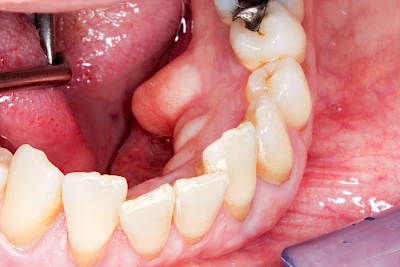

Überbeine im Bereich der Kiefer sind gar nicht so selten. Häufiger im Bereich der Seitenzähne unterhalb des Zahnfleisches, aber auch in der Mitte vom Gaumen. Überbeine haben in dem Sinne keinen Krankheitswert, müssen also nicht operativ entfernt werden, wenn diese nicht stören. Überbeine können ein Anzeichen für Knirschen und Pressen sein.